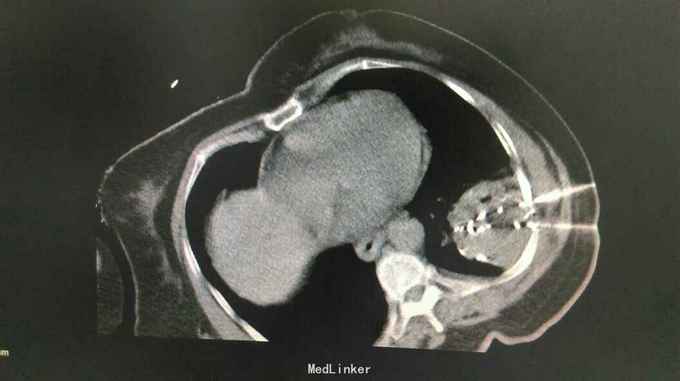

查体:体温:36℃,脉搏:86次/分,呼吸:21次/分,血压:137/81mmHg,胸廓无畸形,两侧对称,双肺呼吸动度一致,左下肺呼吸音减弱,未闻及干湿罗音。心率:86次/分,律齐,心前区及各瓣膜听诊区未闻及杂音,腹软,无压痛及反跳痛。双下肢体无水肿。 辅助检查:胸部CT示:左肺下叶,双肺多发转移灶。于10月16日行左侧胸腔积液穿刺引流,胸水病理检查示:可见少许核异型细胞,考虑为腺癌细胞 颅脑MR检查示:右侧小脑半球两处异常信号,转移瘤可能,右侧放射冠区陈旧性腔梗。

中医诊断: 肺积 正虚瘀结 西医诊断: 1.左肺占位性病变:双肺转移? 2.2型糖尿病 3.冠状动脉粥样硬化性心脏病 治疗经过:,于10月8日下午行左肺占位穿刺活检,病理回报示:不除外细支气管肺泡癌。于10月12日下午行左肺癌碘125粒源植入术,围手术期给予抗感染、支持治疗。于10月16日行左侧胸腔积液穿刺引流,胸水病理检查示:可见少许核异型细胞,考虑为腺癌细胞,给予胸腔药物灌注治疗。于10月25日-29日给予患者生物细胞免疫DC+CIK治疗。 患者家属拒绝静脉化疗,给予口服特罗凯治疗!

患者治疗后一月余行肺ct检查病灶肺部病灶明显缩小!口服特罗凯治疗耙向治疗!